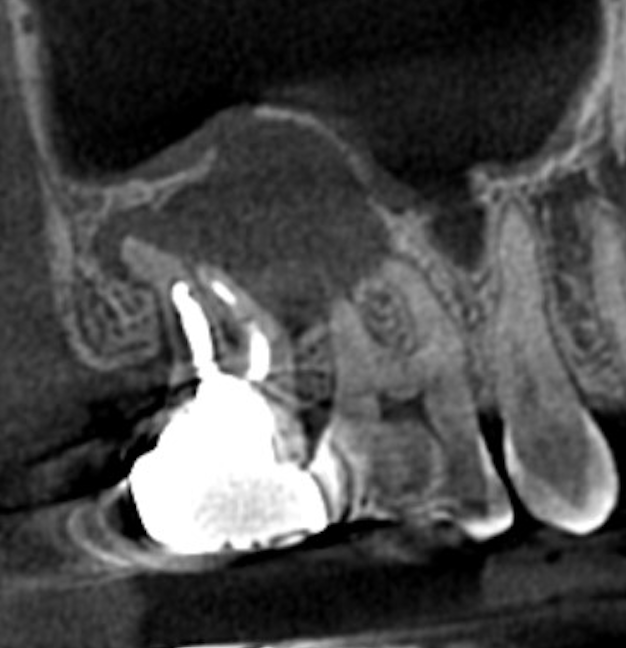

■ 術前の状態

レントゲン・CTでは、

根尖部に上顎洞に達する大きな透過像(病変)を認めました。

現在は痛みがない状態でしたが、

これは「治癒」ではなく、

👉 感染が慢性化し、症状が出にくくなっている状態

と考えられます。

また本症例では、

- 根管の湾曲が約30度と強い

- 遠心に縁下カリエスを認める

- 根尖部に吸収像(構造の破壊)を認める

という状態でした。

特に根尖部に関しては、

本来の解剖学的形態が失われている状態であり、

根管内からのアプローチのみでの改善は難しいと判断されました。